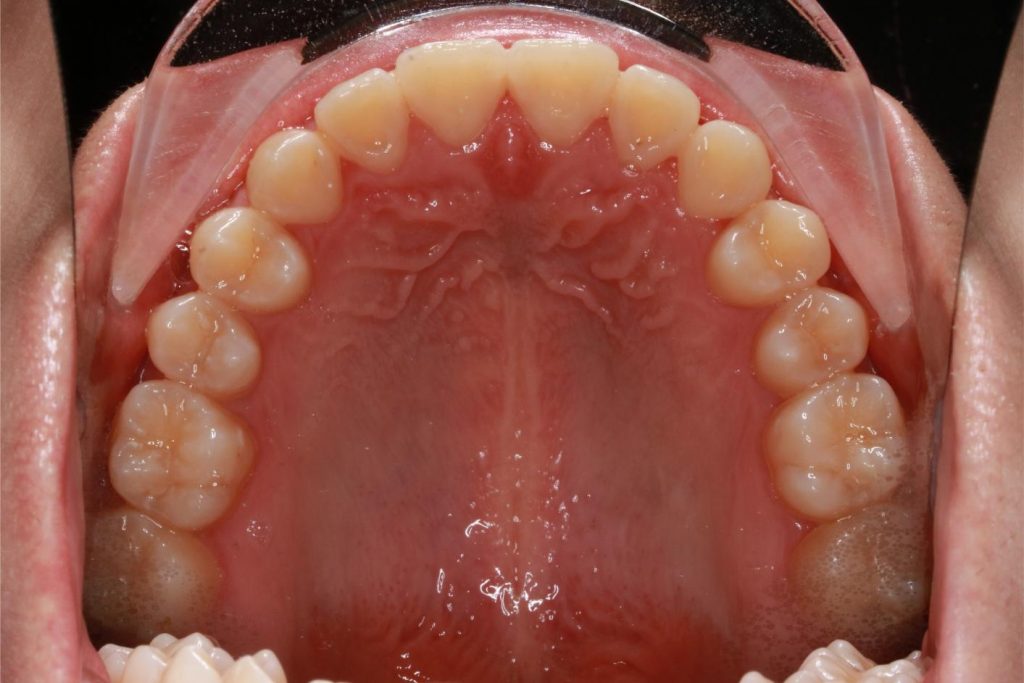

Before and After Images